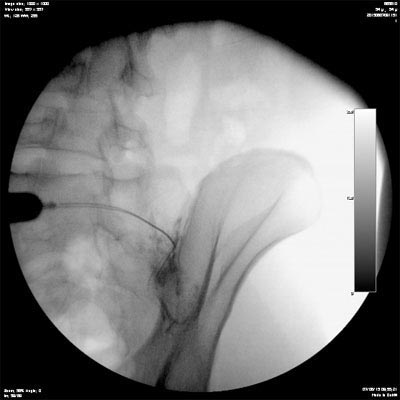

A infiltração é realizada em centro cirúrgico com o paciente sedado e com auxilio da radioscopia ( maquina de raio X). A ponta da agulha deve ser posicionada no interior da articulação sacro ilíaca e então é injetado contraste para verificação de sua posição.

Na figura ao lado é possível ver a colocação do contraste no interior da articulação sacro ilíaca.